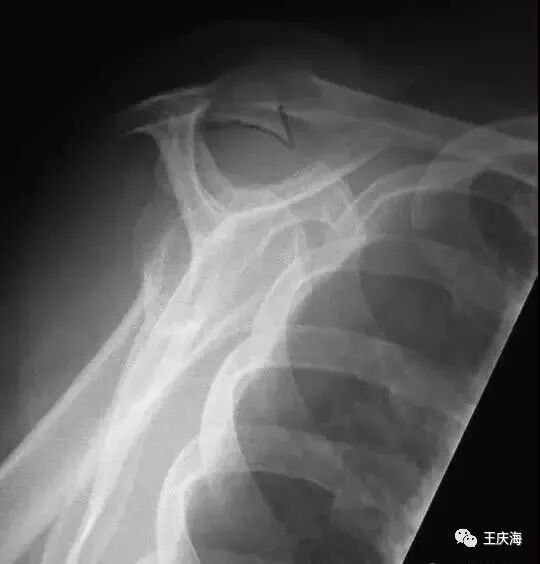

(1)X片:常规拍摄肩关节正位及冈上肌出口位X线片。典型改变包括肩峰下表面硬化和骨赘形成、大结节硬化及囊性变。通过冈上肌出口位可以评价肩峰的形状和厚度。

Bigliani将肩峰形状分为三型:Ⅰ型为平直形肩峰,Ⅱ型为弧型肩峰,Ⅲ型为钩状肩峰。

Snyder根据肩峰厚度将肩峰分为三型:Ⅰ型小于8mm,Ⅱ型8~12mm,Ⅲ型大于12mm。上述分类对于决定术中切除肩峰骨质的数量有重要意义。